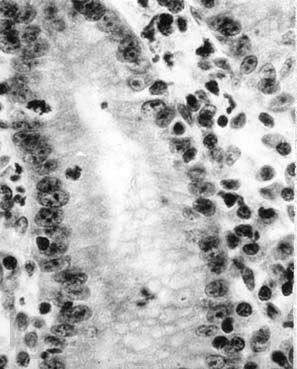

В небольшой по объему монографии представлена краткая анатомо-гистологическая характеристика нормальной слизистой оболочки желудка и двенадцатиперстной кишки, рассматривается морфологическая классификация гастритов и гастропатий, а также сущность дистрофических, воспалительных и дисрегенераторных изменений слизистой оболочки желудка при различных формах гастродуоденальной патологии. Приводятся краткие сведения об основных правилах гистологической техники, знание которых необходимо клиницисту. Основная цель пособия — дать молодому врачу представление об основах морфологической диагностики заболеваний желудка. Книга также может быть полезной для первичного образования и совершенствования гастроэнтерологов, клинических морфологов, эндоскопистов, а также для врачей других специальностей.